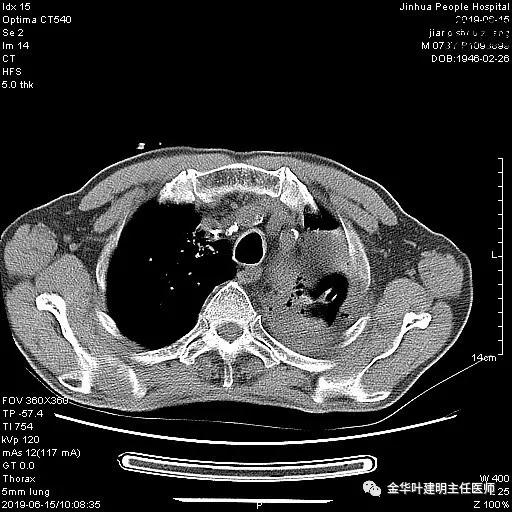

术前检查冠脉CT示:左冠前降支近段多发钙化斑块伴管腔重度狭窄(约85%),建议DSA检查。但追问病史以往平时无胸痛或胸闷症状,运动试验提示可疑阳性(上斜型压低),活动后胸闷气闭症状不明显,既往否认高血压、糖尿病。所以经过心内科会诊讨论,认为还是可以进行手术。术前冠状动脉CT示:

以上是肺窗表现,下面为纵隔窗影像: